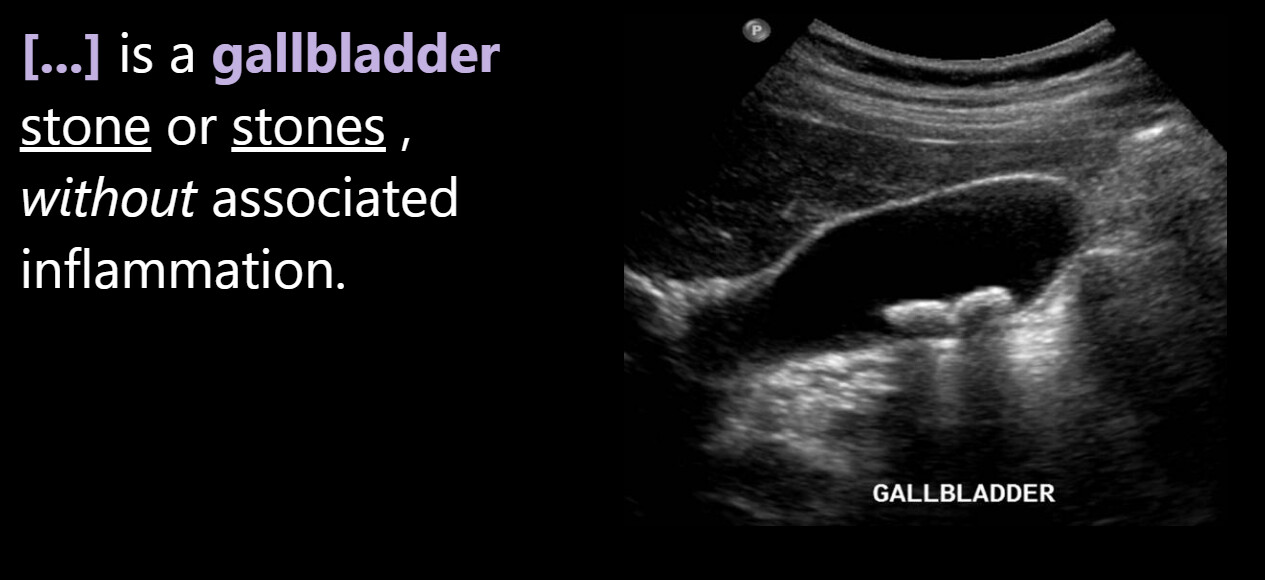

What do the cards look like?

Front:

Back: